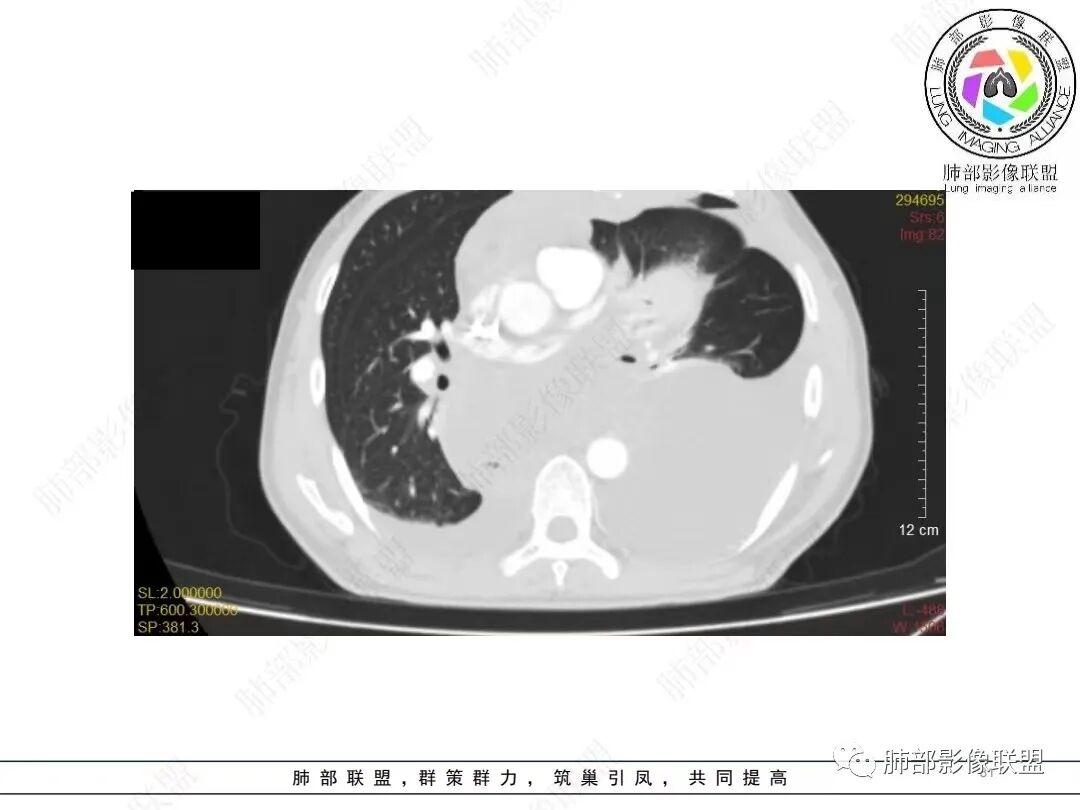

目前的图:主要是胸部的病灶。胸膜弥漫斑块状增厚。强化明显,内部血管漂浮。前纵隔部分病灶强化偏低。

累及多个腔隙、特别是后纵隔、胸膜为主

2.影像学特点:病变范围相当广泛,多发块状影累及纵隔、胸膜、前胸壁(胸大肌下)、前上腹壁等。胸膜弥漫性斑状增厚为主,明显强化,纵隔旁椭圆形块影较密实,沿胸膜分布趋势,未见支气管等结构进入。后纵隔块影较大,占位效应明显,肺静脉受累狭窄。双侧胸腔积液。

3.总结: 多发块影,边界不清,占位效应明显,通常符合恶性肿瘤。两肺未见明确支气管相关块影或结节影,支气管肺癌的判断似乎缺乏立足点,前纵隔、胸膜以及胸腹壁块影也不是支气管肺癌的常见转移途径。

非上皮来源的恶性间叶组织肿瘤应当纳入视线,广泛性侵犯,区域性转移等等,梭形细胞瘤、原始神经外胚叶肿瘤(PNET)、恶性胸膜间皮瘤等等,如果病灶有区域分布优势,如本例的左侧胸膜改变,可以想到胸膜间皮瘤可能性。